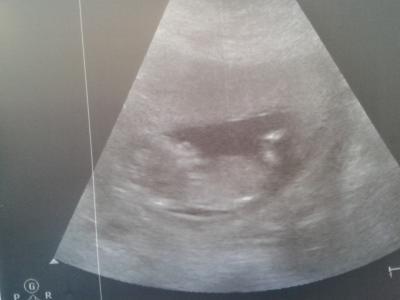

Guten Morgen, ich komme grade vom Frauenarzt zurück. Und bin noch total aufgeregt und happy. Unser kleines ist schon 6,7cm lang (SSL) und hatte wohl grade Turnstunde. Es hat mächtig geboxt und getreten - es war soooooo toll das zu sehen. Ich bin heute 12+3 und mein Arzt sagte das es zu 70-80% ein Mädchen wird. Ich kann das nicht so nicht so nicht glauben, zum einen ist das doch noch ganz schön früh und zum anderen war es so aktiv das er kaum ein Bild hinbekommen hat.

Bild zu Zurück vom FA - Forum für Mai - Mamis